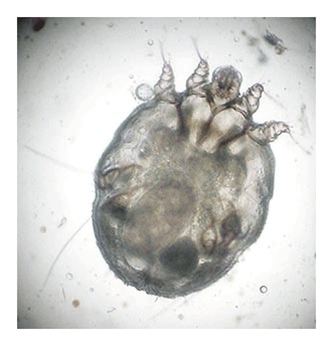

Scabiesmiden kan påvises i mikroskop eller ved dermoskopi

Med godt lys og eventuelt med lup hentes det sorte punkt, som repræsenterer en levende scabiesmide direkte ud fra midegangen, fx med en knappenål - miden sidder fast på spidsen

Den overføres til et objektglas og identificeres i lysmikroskop med mindste forstørrelse

Sarcoptes scabiei var hominis

Hunmiden er 0,3-0,5 mm lang, og kan netop ses med det blotte øje

Hunnen graver gange i stratum corneum og lægger dagligt 2-3 æg, der klækkes som larver efter 3-4 dage

Larverne bevæger sig til hudoverfladen, hvor de modner til voksne